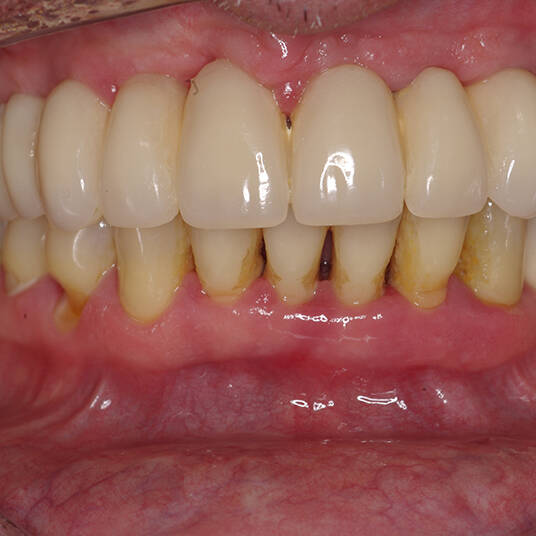

Na Clínica Pontes Odontologia, somos referência em implantes dentários em Fortaleza, oferecendo tratamentos de alta qualidade e tecnologia de ponta. Os implantes dentários são estruturas de titânio posicionadas cirurgicamente no osso maxilar ou mandibular para substituir as raízes dos dentes ausentes. Essa técnica permite a fixação de próteses personalizadas, restaurando a função mastigatória, a estética e a autoestima dos nossos pacientes.

Utilizamos a tecnologia CAD CAM, um sistema avançado que possibilita a confecção precisa das próteses dentárias diretamente sobre os implantes. Esse método inovador garante um ajuste perfeito, um resultado estético superior e proporciona muito mais conforto e durabilidade. Com o CAD CAM, nossos pacientes contam com um processo mais rápido e previsível para alcançar o sorriso desejado.

Nosso compromisso é oferecer um tratamento de excelência, com profissionais especializados e tecnologia de última geração para implantes dentários em Fortaleza. Venha nos visitar e descubra por que a Clínica Pontes Odontologia é referência em implantes dentários em Fortaleza, devolvendo sorrisos e qualidade de vida aos nossos pacientes.